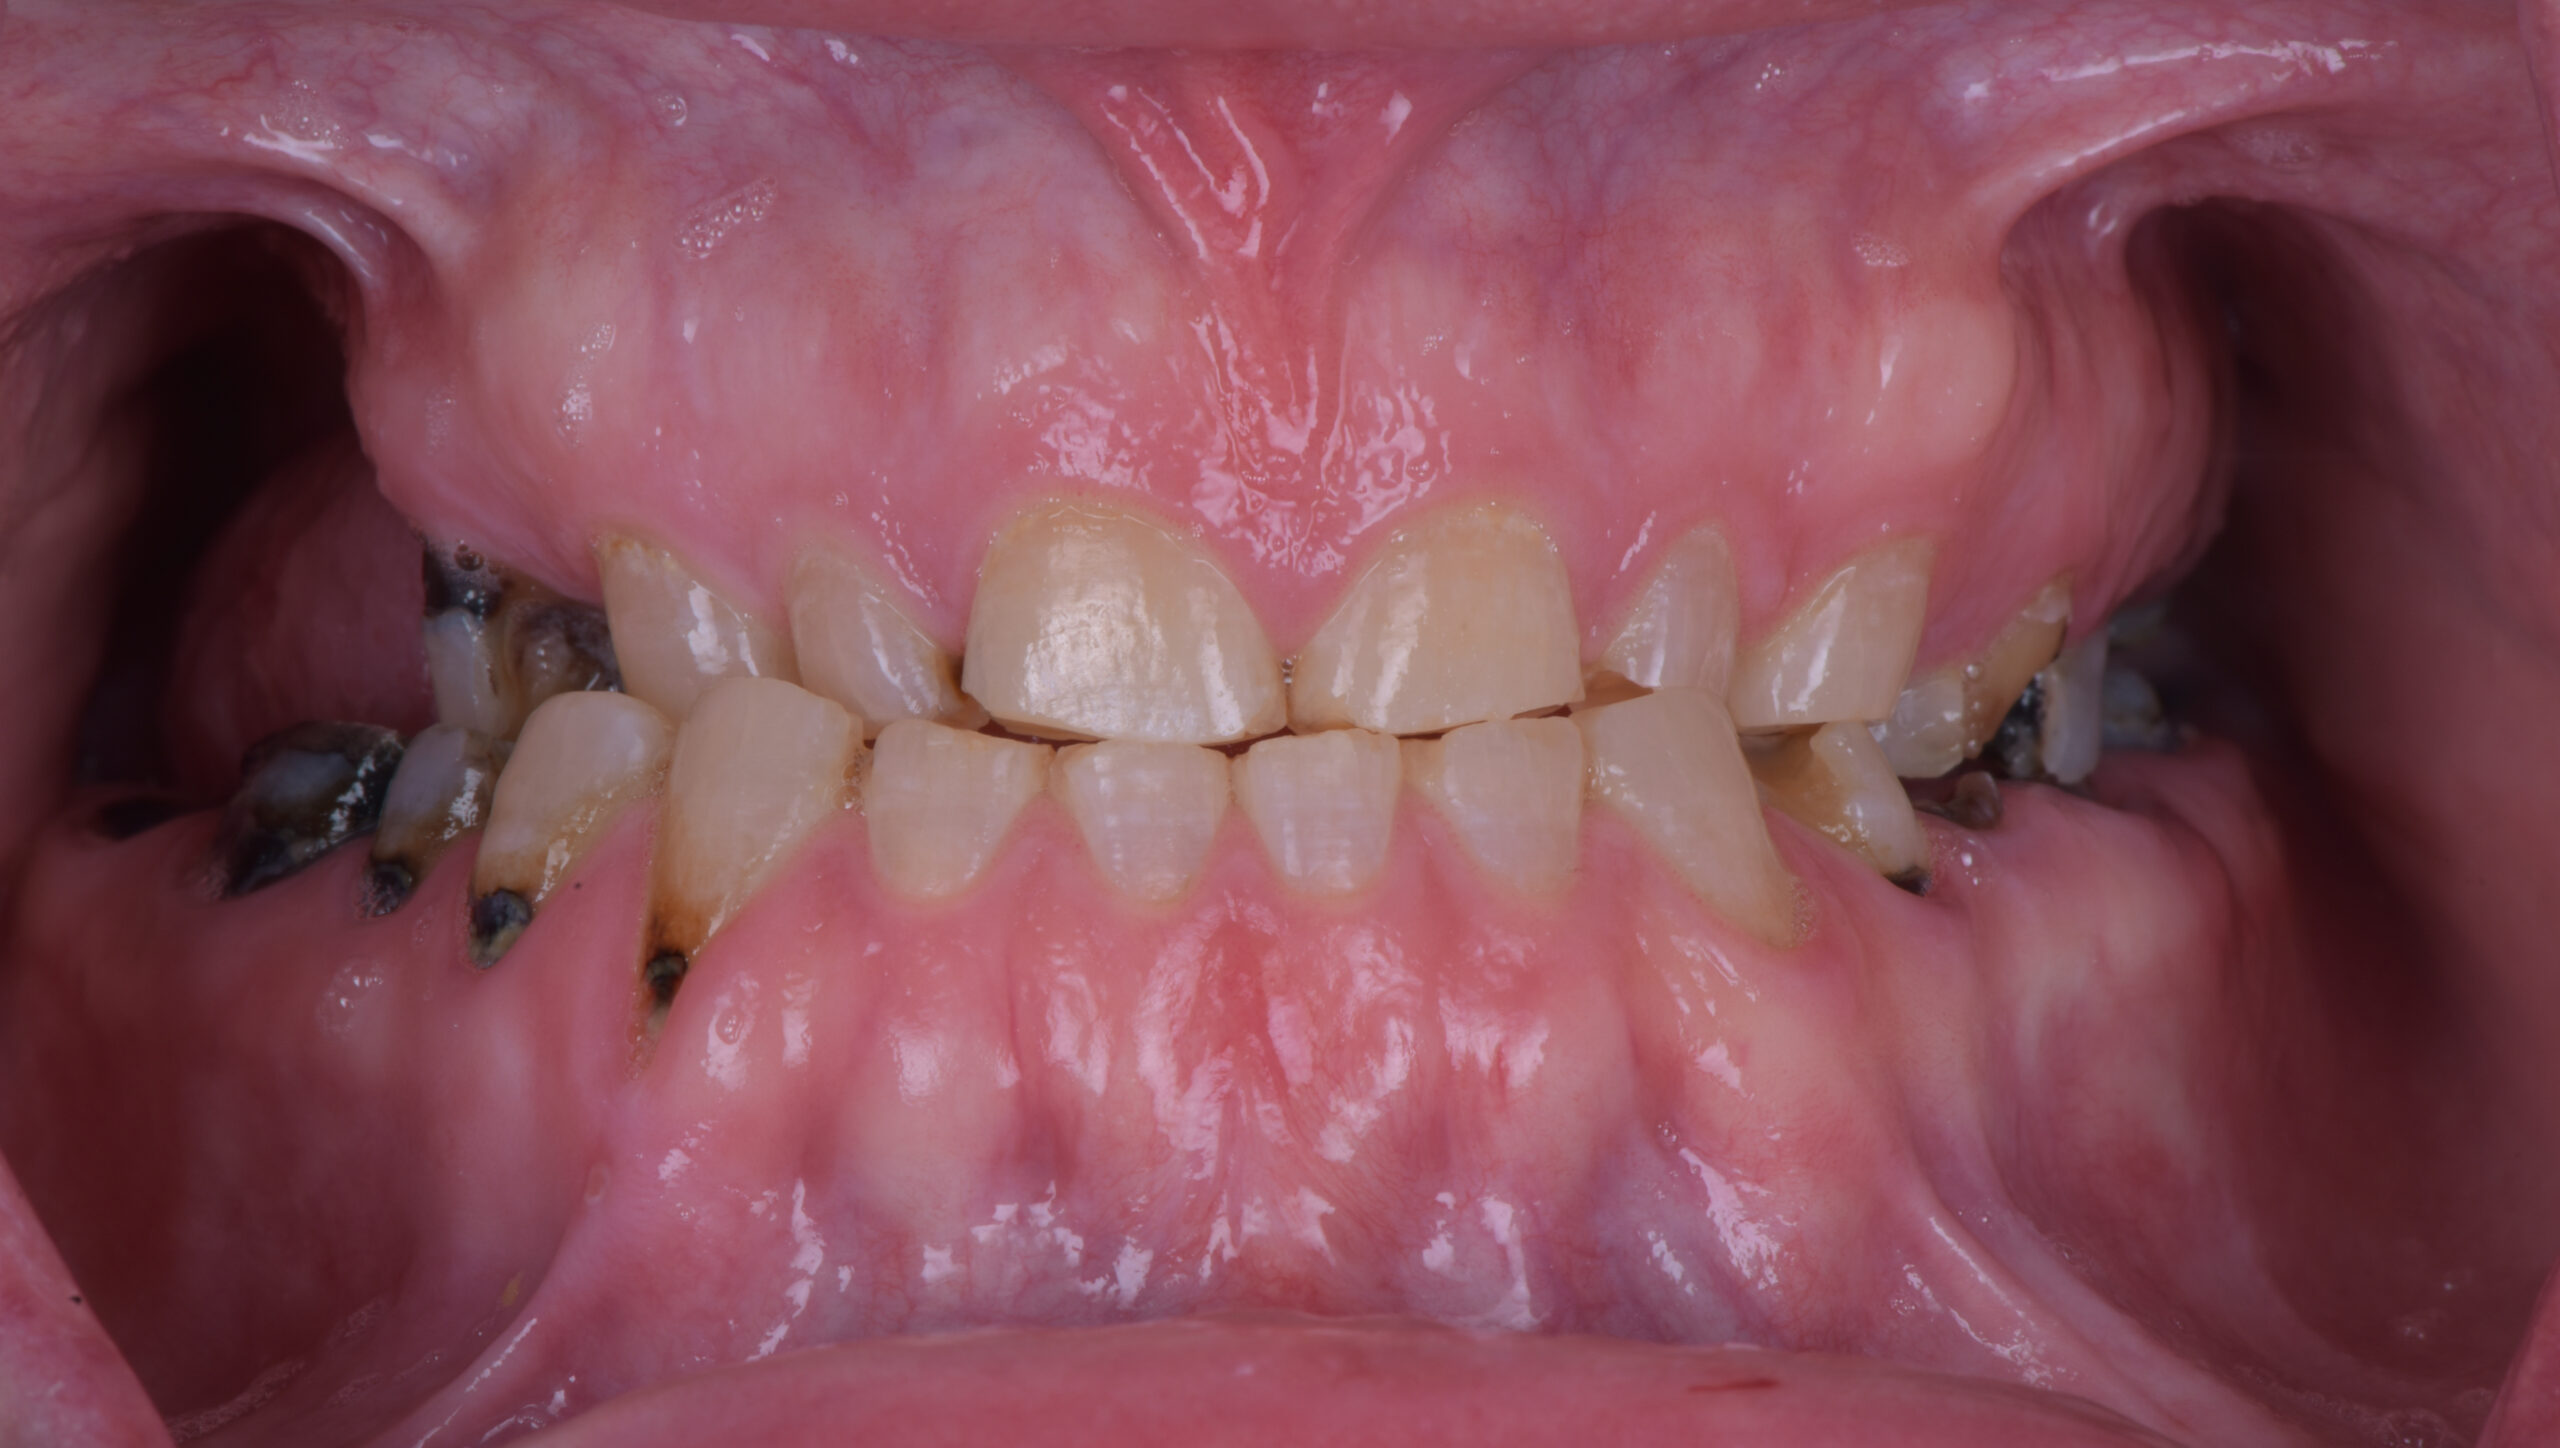

歯ぎしりがある患者さんで実際に起きている問題

名古屋で診療していると、

歯ぎしりがある患者さんのインプラント相談では

ある共通した傾向があります。

それは

奥歯の破折や被せ物のトラブルを経験しているケースです。

例えば次のような状態です。

・奥歯の被せ物が何度も割れている

・セラミックが欠ける

・歯の摩耗が進んでいる

このような症例では

歯ぎしりによる咬合力の影響が疑われます。

咬耗とは

歯が長年の咬合力によって摩耗する現象です。

名古屋の患者さんでも

50代以降では咬耗が進行しているケースが多く見られます。